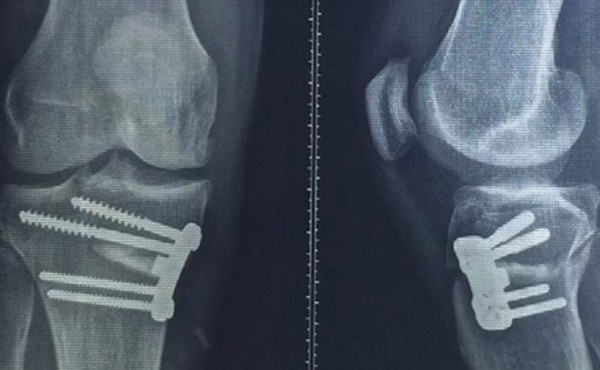

Apenas un mes después de tomar tamaña decisión, tuvo que meterse al quirófano por primera vez en su carrera para operarse su maltrecha rodilla derecha. Mientras ensaya la primera etapa de la recuperación, decidió subir imágenes de su situación y las placas que le realizaron a su Instagram, donde tiene una activa relación con sus fanáticos.

Allí se pueden ver en detalle los tornillos que debieron colocarle en el centro médico de Corinthians para adecuar la zona afectada. Si bien nunca había sido intervenido, había recibido varias infiltraciones en el sitio de la lesión.